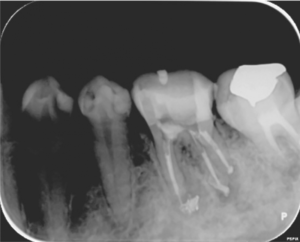

1ヶ月後

根の治療1か月後にグラスファイバーの芯棒を用いた歯の土台(根の治療を行った場合に行う治療です)を立てた際のレントゲン写真です。まだ根の先の骨の溶けている部分の大きさは変わりません。

2ヶ月後

根の治療2か月後のレントゲン写真です。矢印の部分の骨の溶けている部分の大きさが小さくなっています。